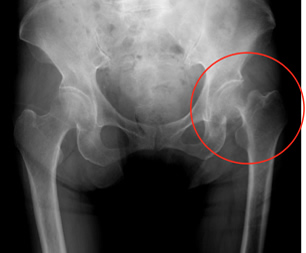

特にずれの大きい大腿骨頸部骨折では主に人工骨頭置換術を行っています(図2)が当科では術後脱臼がしにくいように可能な限り筋腱や関節包を温存・修復する方法(CPP法やERP法)で行っており良好な結果を得ております。

図2-1

大腿骨頸部骨折 人工骨頭術前

図2-2

人工骨頭置換術後

図2-1

大腿骨頸部骨折 人工骨頭術前

図2-2

人工骨頭置換術後